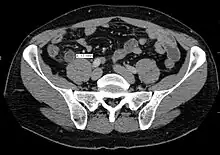

Computed tomography

Where it is readily available, computed tomography (CT) has become frequently used, especially in people whose diagnosis is not obvious on history and physical examination. Although some concerns about interpretation are identified, a 2019 Cochrane review found that sensitivity and specificity of CT for the diagnosis of acute appendicitis in adults was high.[59] Concerns about radiation tend to limit use of CT in pregnant women and children, especially with the increasingly widespread usage of MRI.[60][61]

The accurate diagnosis of appendicitis is multi-tiered, with the size of the appendix having the strongest positive predictive value, while indirect features can either increase or decrease sensitivity and specificity. A size of over 6 mm is both 95% sensitive and specific for appendicitis.[62]

However, because the appendix can be filled with fecal material, causing intraluminal distention, this criterion has shown limited utility in more recent meta-analyses.[63] This is as opposed to ultrasound, in which the wall of the appendix can be more easily distinguished from intraluminal feces. In such scenarios, ancillary features such as increased wall enhancement as compared to adjacent bowel and inflammation of the surrounding fat, or fat stranding, can be supportive of the diagnosis. However, their absence does not preclude it. In severe cases with perforation, an adjacent phlegmon or abscess can be seen. Dense fluid layering in the pelvis can also result, related to either pus or enteric spillage. When patients are thin or younger, the relative absence of fat can make the appendix and surrounding fat stranding difficult to see.[63]